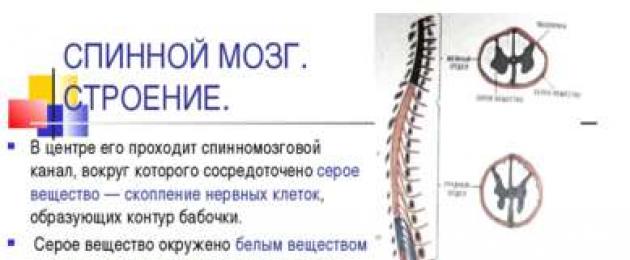

Спинной мозг и двигательная активность: Важные аспекты